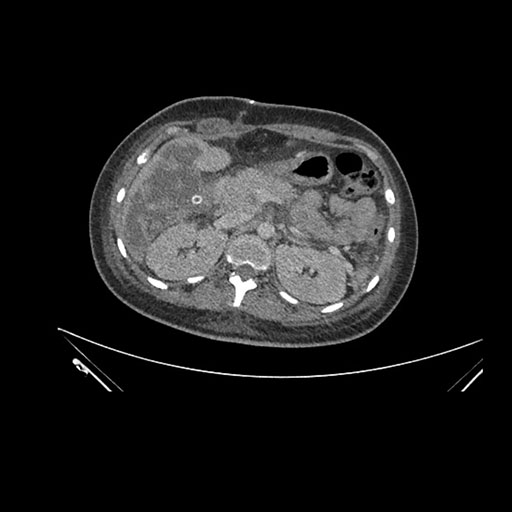

Imaging Analysis

Look through the patient's CT scan to identify any areas of concern for the necessary procedure.

Coronal Arterial

Based on initial findings, which issue(s) would you be most concerned about?